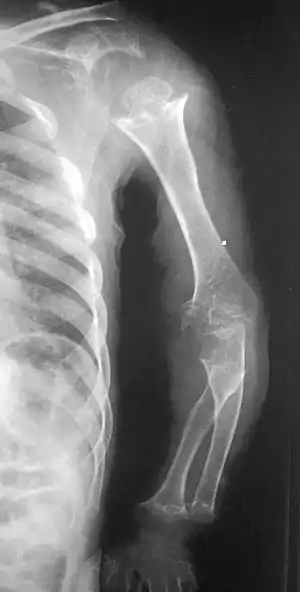

| Pseudoachondroplasia. Shoulders and Humeri. Note the dysplastic proximal humeral epiphyses, metaphyseal broadening, irregularity and metaphyseal line of ossification. These changes are collectively known as "rachitic-like changes". Lesions are bilateral and symmetrical. | |

Skeletal radiography

Accurate assessment of plain radiographic findings remains an important contributor to diagnosis of pseudoachondroplasia. It is noteworthy that vertebral radiographic abnormalities tend to resolve over time. Epiphyseal abnormalities tend to run a progressive course. Patients usually suffer early-onset arthritis of hips and knees. Many unique skeletal radiographic abnormalities of patients with pseudoachondroplasia have been reported in the literature.[2][7][4]

- Dysplastic/hypoplastic epiphyses especially of shoulders and around the knees.

- Metaphyseal broadening, irregularity and metaphyseal line of ossification. These abnormalities that are typically encountered in proximal humerus and around the knees are collectively known as “rachitic-like changes”.

- Radiographic lesions of the appendicular skeleton are typically bilateral and symmetric.